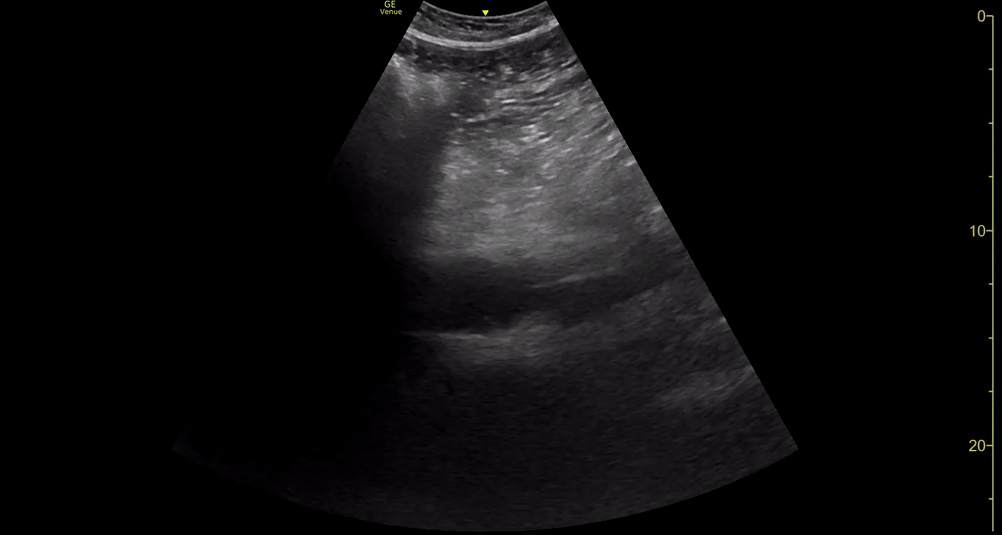

ABDOMINAL AORTA

Identify the vertebral body, with the aorta directly anterior to it, and adjust the depth and gain settings to optimize visualization. It is essential to identify and differentiate the two major vessels: inferior vena cava (IVC) and aorta. The IVC is parallel and to the right, featuring thinner walls and collapsibility during inspiration. However, owing to transmitted pulsation, it may be misidentified as the aorta, particularly in longitudinal section. The identification of other vessels, namely the coeliac trunk and superior mesenteric artery (SMA), is also helpful for differentiating the aorta from the IVC. The coeliac trunk is conformed by the common hepatic artery and the splenic artery, rendering the classic “seagull sign”.

Once the aorta is identified, measure its diameter from outer to outer wall, as inner wall measurements may underestimate the diameter due to mural thrombus (false negative). While maintaining the transverse orientation, slide the probe distally until the aortic bifurcation and measure the diameter at its middle and distal portions. Then, rotate the probe to the longitudinal position, which is needed to identify saccular aneurysms. Attempt to obtain a view of the aorta that includes the origin of the coeliac trunk or SMA, and measure the AP diameter. Remember, AAA is not ruled out unless the entire length of the abdominal aorta can be visualized and measured.

Areas of bowel gas will be identified and these obstruct the view of the aorta. These areas may be reduced by moving the transducer laterally, rotating the patient or by using the transducer to massage them away from the area of interest. However just keep moving the transducer inferiorly and the aorta will soon be in view again